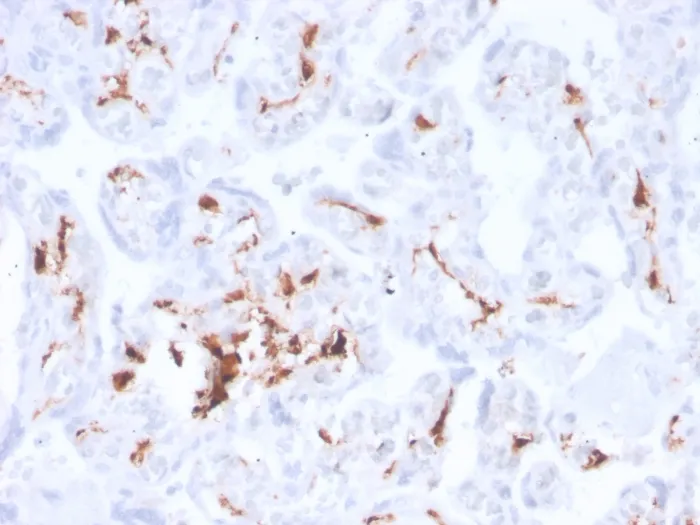

Recognizes a protein of 83 kDa, which is identified as Factor XIIIa. It has been identified in platelets, megakaryocytes, and fibroblast-like mesenchymal or histiocytic cells in the placenta, uterus, and prostate, monocytes and macrophages and dermal dendritic cells. Anti-factor XIIIa has been found to be useful in differentiating between dermatofibroma (almost all cases are positive), dermatofibrosarcoma protuberans (-/ ) and desmoplastic malignant melanoma (-). Anti-factor XIIIa positivity is also seen in capillary hemagioblastoma, hemangioendothelioma, hemangiopericytoma, xanthogranuloma, xanthoma, hepatocellular carcinoma, glomus tumor, and meningioma. Primary antibodies are available purified, or with a selection of fluorescent CF® Dyes and other labels. CF® Dyes offer exceptional brightness and photostability. Note: Conjugates of blue fluorescent dyes like CF®405S and CF®405M are not recommended for detecting low abundance targets, because blue dyes have lower fluorescence and can give higher non-specific background than other dye colors.Synonyms:

IHC, FFPEPositive Control: